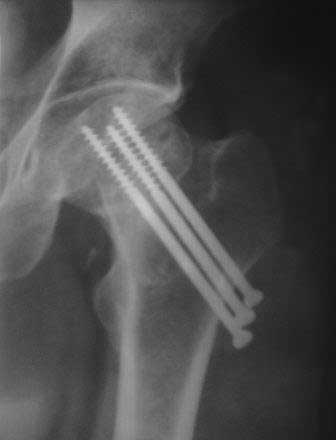

В данном случае не стал бы разбирать ошибки остесинтеза. На снимке, возможно, из-за большого диаметра шейки шурупы кажутся менее тонкими, чем в 6.5мм. Если установлены стандартные шурупы, тогда, возможно, это случай,

где вместе трех шурупов можно было бы установить 4 в виде ромба?

Отложите вопрос о протезировании еще на 3 месяца, есть шанс срастить перелом при исключении нагрузки. При выполнении органосохраняющих операций результат будет хуже, чем при протезировании

При явном ложном суставе у молодых тактика органосохранная, и из всех видов реконструкционной операции вальгусная остеотомия показала

наилучший результат. А детали операции неоднократно разбирали на сайте.